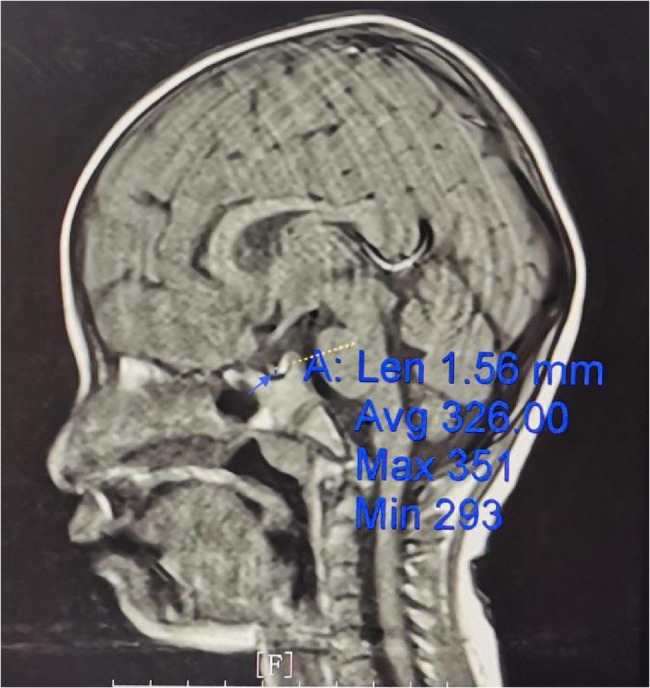

Goltz综合征,又称局灶性真皮发育不全,是一种由PORCN基因突变引起的x连锁显性遗传疾病,主要表现为影响皮肤、头发、骨骼、牙齿和眼睛的发育障碍。本研究报告一例广泛的皮肤发育不良,肢体畸形,身材矮小。1个月大的孩子的基因组DNA全外显子组测序显示PORCN基因突变,证实了戈尔茨综合征的诊断。当她3岁的时候,她的体重下降了

Goltz syndrome, also known as focal dermal hypoplasia, is an X-linked dominant genetic disorder caused by mutations in the PORCN gene, mainly characterized by developmental impairments affecting the skin, hair, bones, teeth, and eyes. This study reports a case with extensive skin dysplasia, limb malformations, and short stature. The genomic DNA whole exome sequencing of the child at 1 month of age revealed a mutation in the PORCN gene, confirming the diagnosis of Goltz syndrome. When she was 3 years old, she suffered from weight loss (W<-3SD) and was short for her age (H<-3SD). The growth hormone stimulation test confirmed growth hormone deficiency. She was treated with long-acting growth hormone (0.2 mg/Kg/week) for 2 years and 9 months, leading to a significant increase in height, with an average annual growth rate of 9.4 cm, without any side effects after three years of follow-up. Goltz syndrome with short stature may be associated with growth hormone deficiency, and long-term growth hormone therapy can achieve clinical benefit.